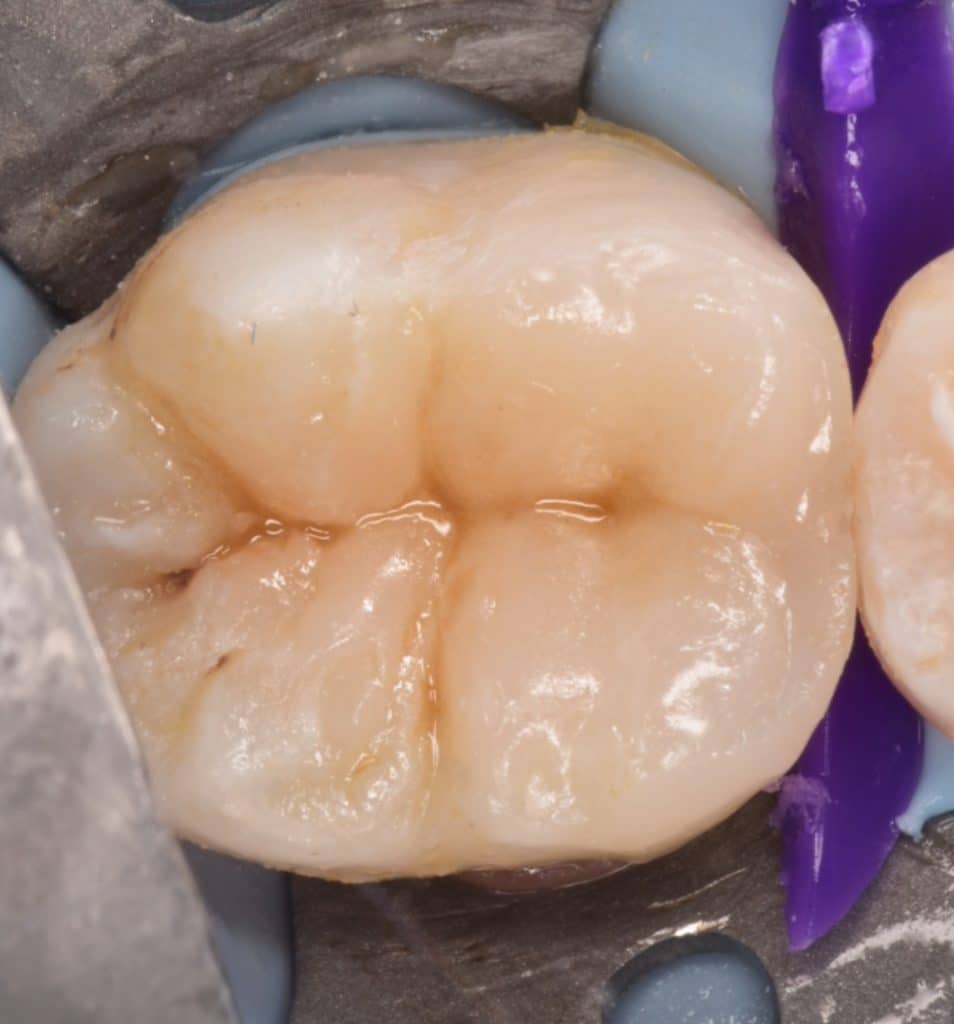

Immediate result

Final result